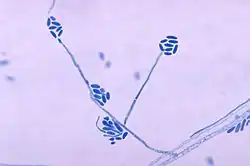

Возбудителями мицетомы являются дейтеромицеты (эумикотическая мицетома) или актиномицеты (актиномицетома) родов Actinomyces, Nocardia, Streptomyces, Actinomadura. Среди грибов встречаются: Madurella grisea, Phialophora cryanescens, Exophiala jeanselmei, Pseudallescheria boydii, Acremonium (Cephalosporium) falciforme, Leptosphaeria senegalensis, Curvularia spp.

Виды грибков мицетомы Nocardia (в том числе Nocardia asteroides и Nocardia brasiliensis) производят желтые споры, и Streptomyces (в том числе Streptomcyes somaliensis) производят желтые или красные споры.